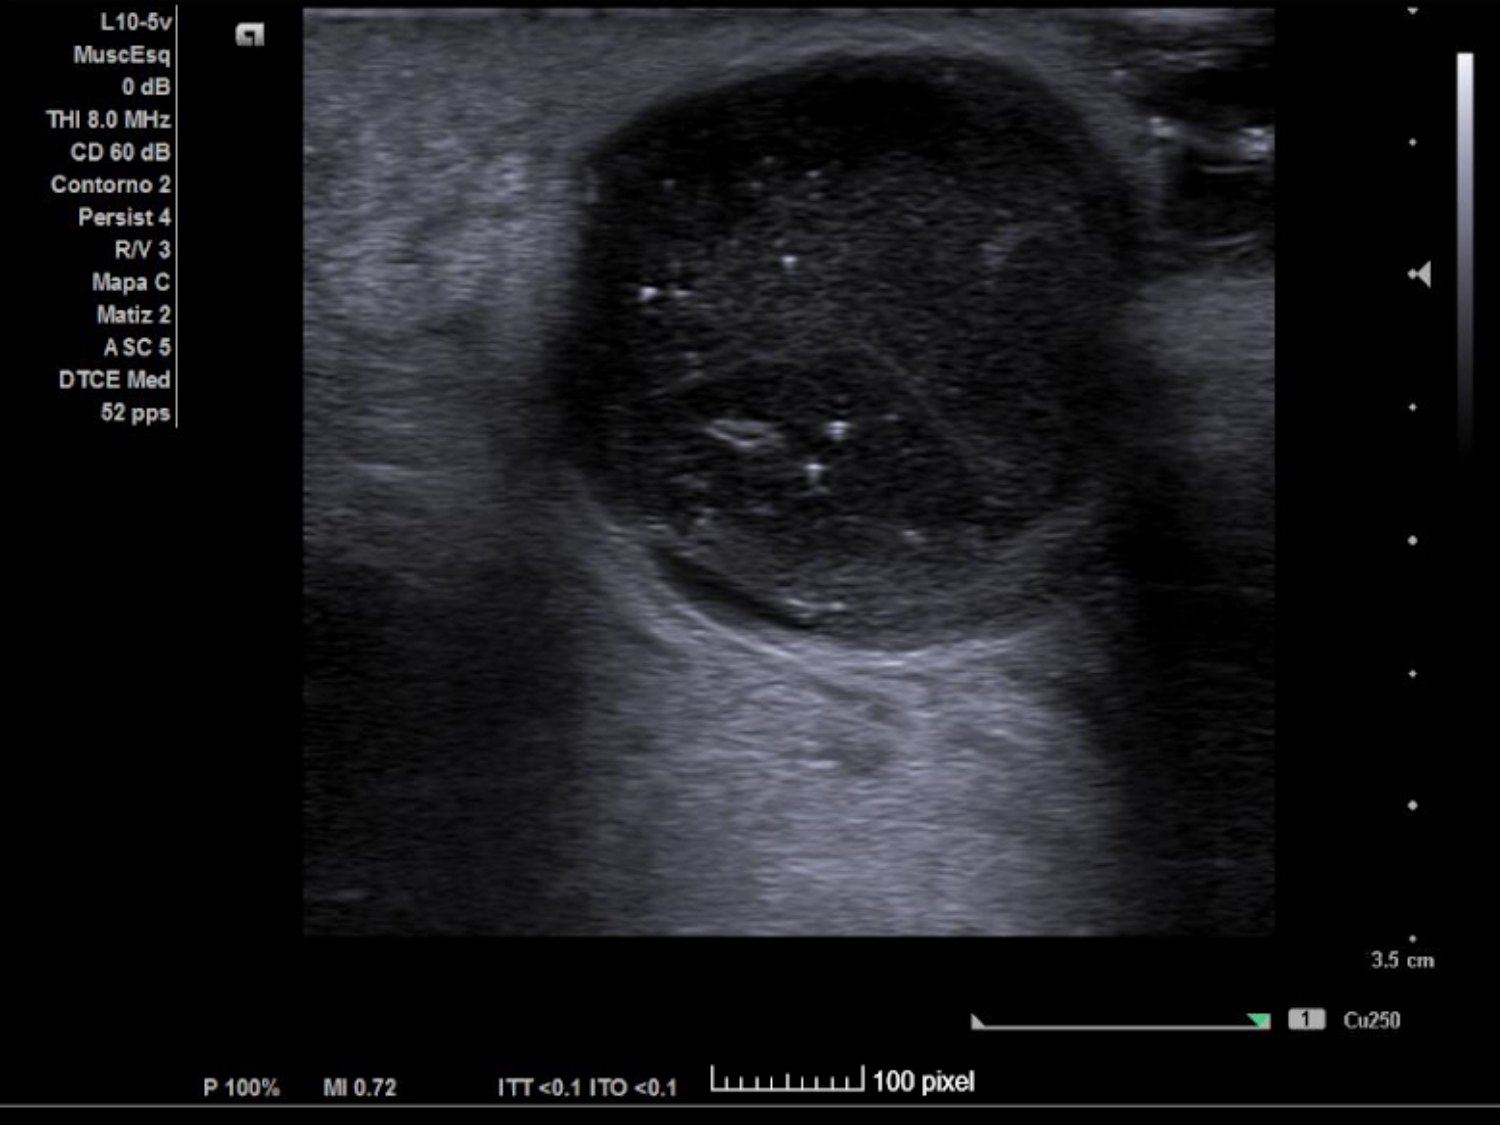

Se realiza ECO POCUS en la que se aprecia un absceso de 23 x 21 mm a menos de 1 cm de profundidad, con fácil acceso a nivel cutáneo y contenido heterogéneo, más anecoico en algunas zonas y poco tabicado.